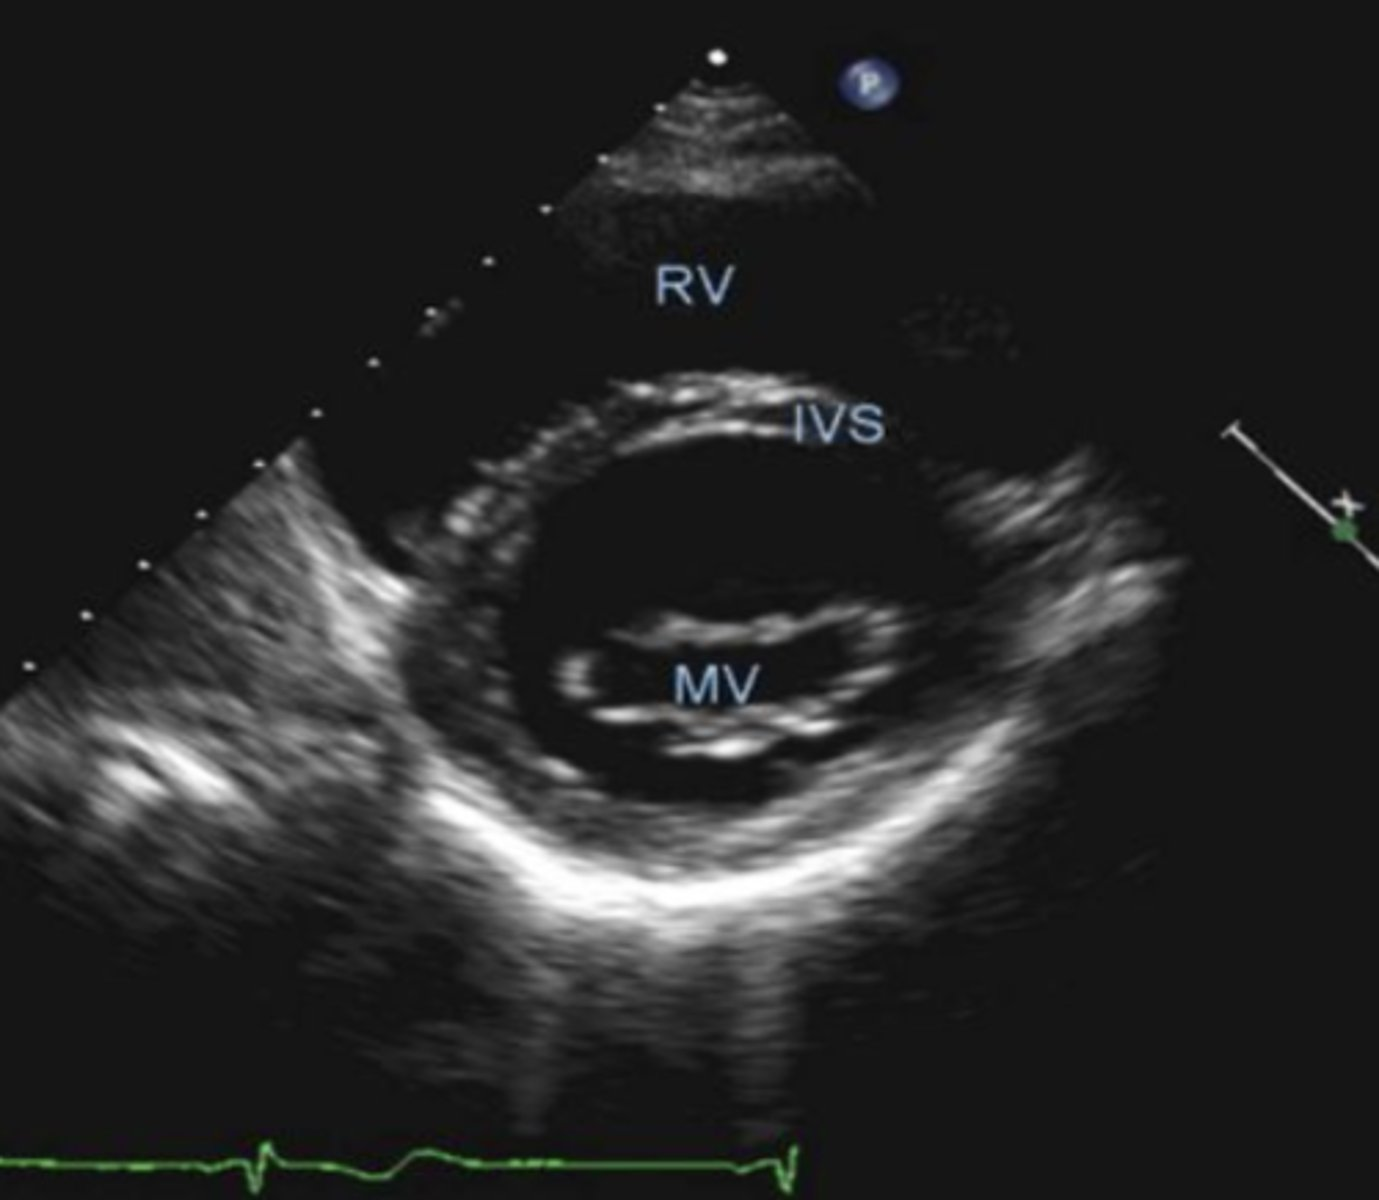

PSSA MV is used to visualize _____

MV